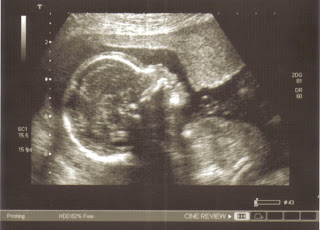

Both the daddy and mommy-to-be do not want to know the sex of the baby eventhough it can be determined now. They said there aren’t many surprises in this world so they want this to be a surprise. How sweet. With Ashley, we were so eager to find out whether it’s a boy or a girl.

Wow, the scan image is so clear! I’m for one who can never resist the temptation to know the gender of the bb.

health freak mommy – yeah…it was very clear but i was trying to scan the lower part to see if i could get anything..very kaypoh lah me.